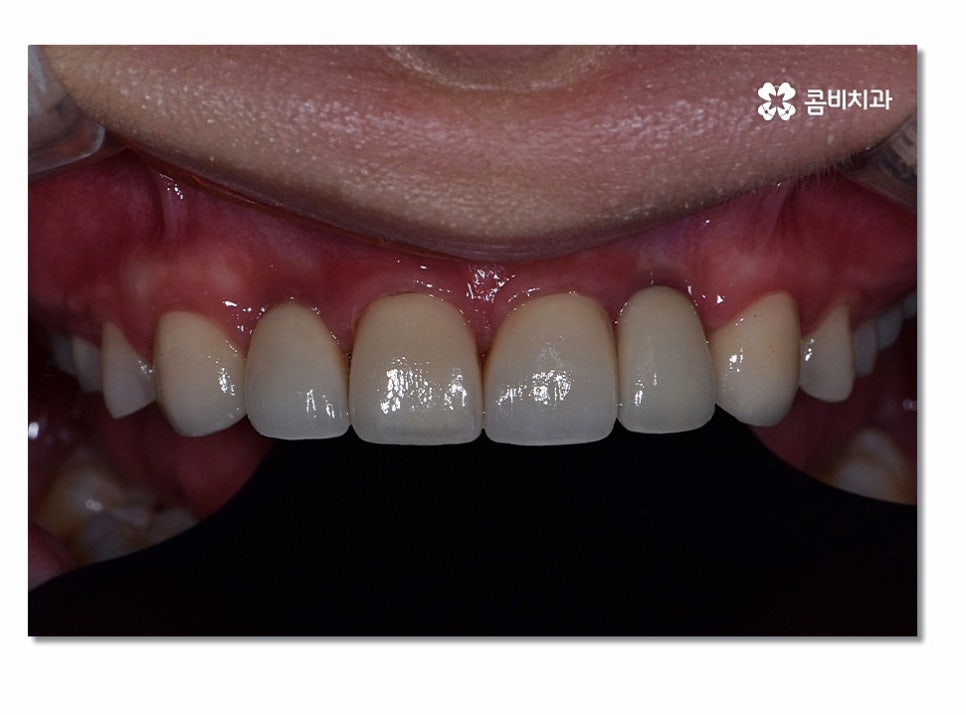

특히 위 환자분의 경우에는 앞니 올 세라믹 치료와

치아교정, 임플란트를 동시에 진행해야 했기 때문에

전체적인 조화와 치료 계획을 철저하게 세울 필요가 있었고

앞니임플란트와 함께 주변 치아가 심미적으로

자연스럽게 어울리면서 교합까지 잘 체크해야 했기 때문에

유독 여러 측면에서 섬세한 치료가 필요했다고 볼 수 있어요.